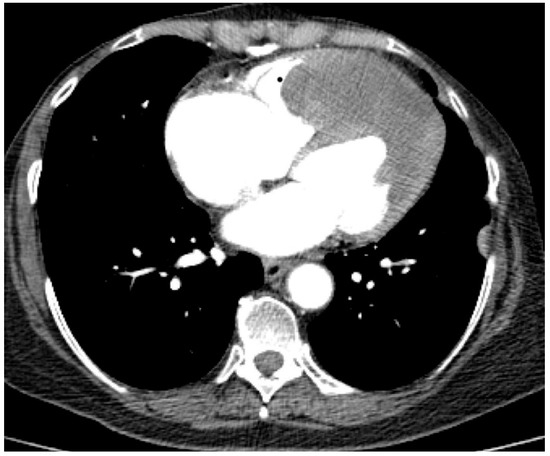

The troponin I level was found to be slightly elevated (90 ng/mL). Coronarography was used to rule out any luminal or anatomical abnormalities. A tumour filling the right ventricle and involving the apex of the left ventricle was identified at transthoracic echocardiography (Figure 3 and Figure 4).

The tumour size and degree of infiltration over the whole apex of the left ventricle were determined by injecting 2 mL of SonoVue (Bracco S.p.A., Milan, Italy) at the level of intra-myocardial contrast in the left ventricle. The presence of microbubbles at this level confirmed the vascularization of the tumour mass. A non-homogeneous right ventricular mass of 88/61/80 mm extending to the left ventricle with areas of necrosis in both ventricles, disseminated lobular nodules on both pulmonary fields measuring 9 mm (right lung), 17 mm (left lung), and right para-tracheal adenopathy were identified on a thoracic CT scan (Figure 5 and Figure 6).

Figure 5. Computed tomography scan: sub-pleural peripheral nodular lesions typical of tumours (abbreviations: CT = cardiac tumour, PLN = pleural nodule, PMN = pulmonary nodule).